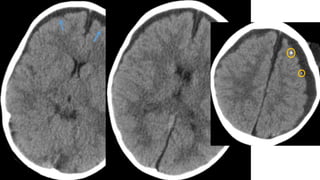

Este documento presenta el caso de un niño de 3 años que sufrió episodios de paresia y alteraciones neurológicas. Exámenes revelaron la presencia de un higroma cerebral que fue drenado. A pesar de una mejoría inicial, el niño continuó presentando síntomas neurológicos intermitentes. Exámenes posteriores identificaron una rara vasculopatía que afecta vasos cerebrales y otros órganos, con un pronóstico grave.